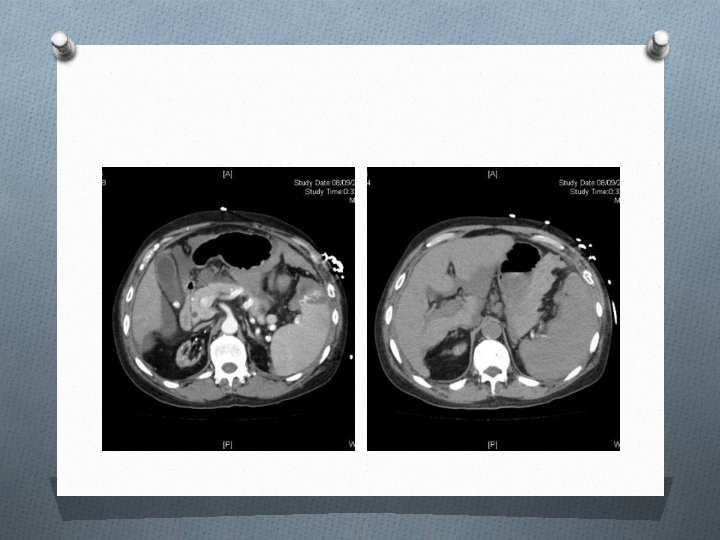

Case 5 O M/56 O History of alcoholic liver cirrhosis with portal hypertension O S/F with left chest wall contusion O BP 84/58 mm. Hg, P 80/min

Question 1 O Describe 3 abnormalities on the CT images (1. 5 marks)

Question 2 O What is the most likely cause of hypotension in the patient? (0. 5 mark)

Question 3 O What is the classification and the grading of this injury? (1 mark)

Question 4 O Suggest 2 treatments if non-operative management is adopted for this patient (1 mark)

Question 5 O Suggest 2 indications of emergency laparotomy for this injury. (1 mark)